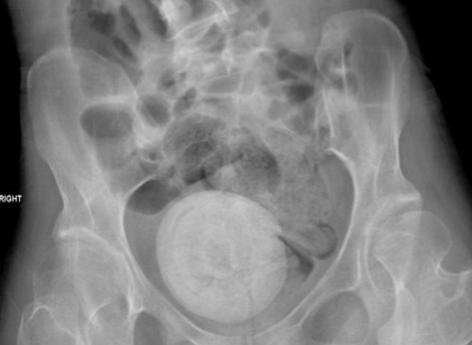

Dans le cas de cette patiente, les médecins ont réalisé un scanner pelvien et abdominal après son arrivée aux urgences. Cela leur a permis de découvrir une masse importante, de forme ronde, dans la zone pelvienne. "Le scanner de l'abdomen et du bassin a montré une structure ronde calcifiée dans le bassin occupant l'espace entre la vessie et le rectum poussant probablement vers le haut de l'utérus occupant l'espace vaginal, décrivent-ils. Il mesure 9 × 10 cm ; un autre calcul obstructif de 1,4 cm a été observé."